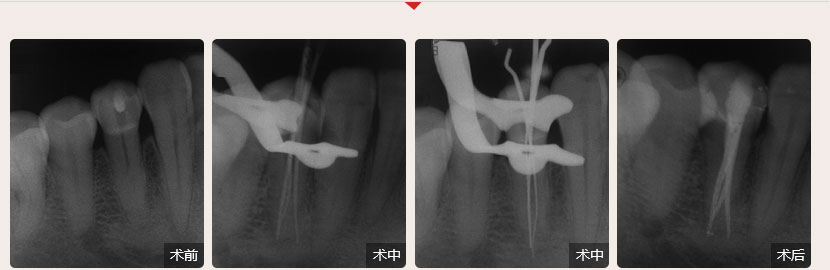

德倫口腔醫(yī)生全國根管治療技術(shù)競賽獲獎案例展示

性別:男        年齡:55歲

牙齒癥狀:急性牙髓炎(左下牙自發(fā)性、陣發(fā)性痛3天)        治療方法:顯微根管治療

疑難點評:操作方面使用根管顯微鏡和超聲波系統(tǒng)細(xì)致尋找和定位根管,根管的敞開度較為完美,維持了根管的原有走向,充填致密,流暢,充填長度準(zhǔn)確。

順德德倫口腔醫(yī)生全國根管治療技術(shù)競賽案例